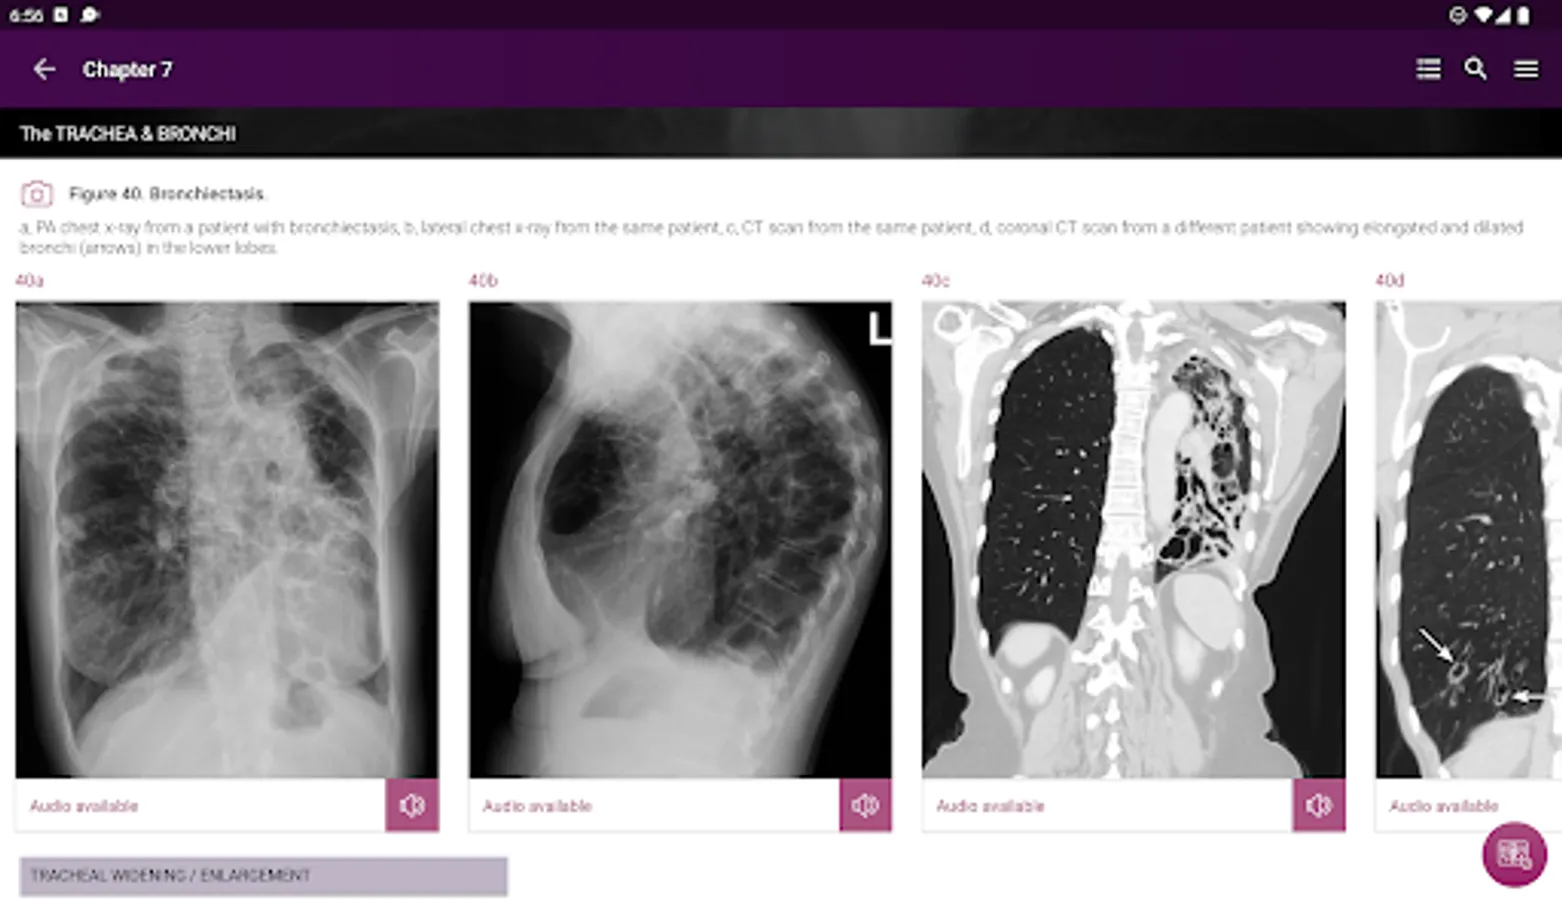

Section II* introduces the concept of radiological zones to give you a starting point in the understanding of the radiological anatomy of the chest. The next chapters review in detail the radiological anatomy of specific anatomical structures, also provide examples of how the x-ray image can change due to pathology. The final chapter explains how the individual structures come together to form the radiological image.